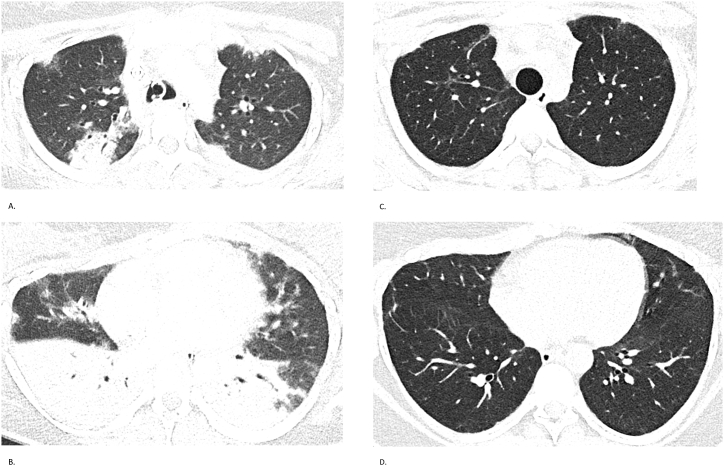

Fig. 1.

Case 1 – Chest CT findings

Serial chest CTs of a 22-year-old woman with anti-MDA5-positive ILD. (A, B) CT on November 25, 2022, shows extensive bilateral ground-glass opacities and consolidations. (C, D) CT on May 28, 2024, demonstrates marked radiological improvement with resolution of acute inflammatory changes and residual subpleural fibrosis.

High-resolution CT of the chest revealed bilateral ground-glass opacities and consolidations with rapidly progressive interstitial lung disease (Fig. 1). Serology was notable for elevated titers of anti-MDA5 antibodies, with a peak anti-MDA5 IgG index of 21 %, declining to 11 % and eventually becoming undetectable after eight months. Initial spirometry in April 2023 demonstrated a severe restrictive ventilatory defect: Forced Vital Capacity (FVC) 1.45 L (45 %). Gradual improvement was observed, reaching FVC 2.05 L (63 %) by September 2024.